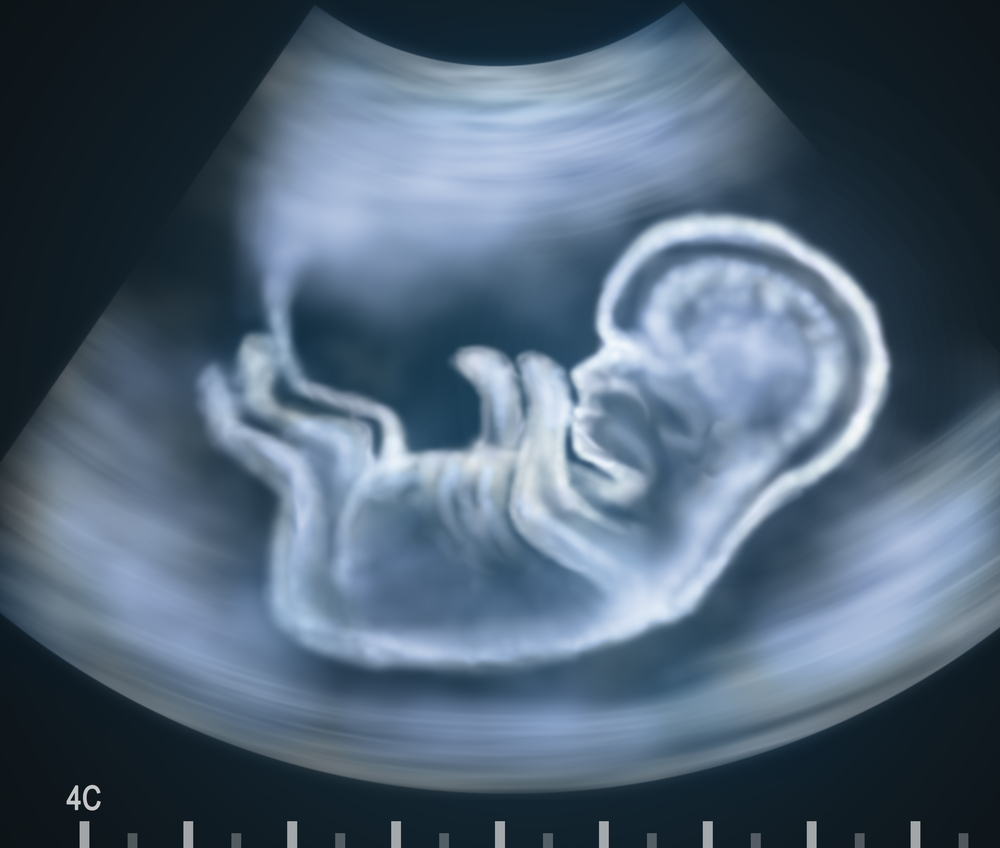

ទារក​មាន​ជំ​ងឺពក​ឆ្អឹង​កង​ខ្នង អាច​ដឹង​តាម​រយៈ​ការ​ពិនិត្យ​អេកូ​ដោយ​គ្រូពេទ្យ​ជំនាញ នៅ​សប្តាហ៍​ទី១២ នៃ​ការ​ពពោះ​ ដែល​ក្នុង​ករណី​ធ្ងន់ធ្ងរ​គ្រូពេទ្យ​នឹង​ឲ្យ​បញ្ឈប់​គភ៌​តែ​ម្តង។ លោកស្រី​វេជ្ជបណ្ឌិត ទី សុវណ្ណរដ្ឋ និយាយ​ថា នៅ​ប្រទេស​ជឿន​លឿន គេ​អាច​ព្យាបាល​ទារក​ដែល​មាន​ជំងឺ​ពក​ឆ្អឹង​ខ្នង​តាំង​ពី​នៅ​ក្នុង​ពោះ​ម្តាយ ដោយ​មិន​ចាំបាច់​រង់ចាំ​ឲ្យ​កូន​កើត​មក​ទើប​វះកាត់​ឆ្អឹង​ខ្នង​បិទ​ឲ្យ​ជិត​វិញ​នោះ​ទេ។